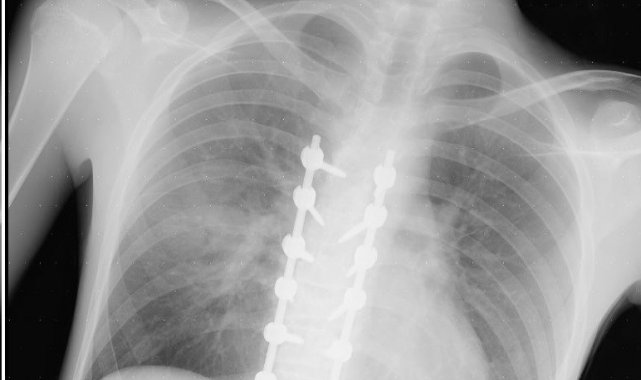

"Beş gün entübe edildi. Ne olacağı belli değildi çıkmama ihtimali vardı. Şükürler olsun doktorlarımız ve Rabbim sayesinde entübeden çıktık. Hatta ciğerin birisinde infilak vardı; ciğer sorunumuzdan dolayı özellikle yoğun bakımda entübediydik. Beş günün sonunda ciğerleri toparlamaya başladı; entübeden çıkarttılar. Solunumu normale döndü. Sırayla sağlığı yerine gelmeye başladı. Bir hafta sonra kolundan ameliyat oldu platin koydular. Omurilikten ameliyat olduk. Omuriliğinde ilk röntgende tek kırık gördüler; üç kemiği birbirine bağlayacaklardı. Sonradan ikinci röntgende üç kırık olduğunu gördük; yedi kemiği birbirine bağladılar. Omuriliğe platin takıldı. 14 tane civatamız var. Şükürler olsun doktorlarımıza, Allah razı olsun. Evladımız gayet iyi, sağlıklı, yerinde. Artık işte suratta, çenede, burunda, elmacık kemiklerinde parçalı kırıklarımız var. Osman Gazi Fakültesi'nde Allah'ın izniyle buradaki hocalarımıza, önce Rabbim'e sonra hocalarımıza emanet çocuğumuz. İnşallah daha iyi olacağız; ben kendi adıma söylüyorum. Çocuğuma, her motora bindiklerinde sürekli kask ve montlarını giymelerini tembihliyordum. Giymediklerinde fırça atıyordum. Eskişehir'de birçok yerde tanınırız, tanırlar. Sevenimiz, eşimiz, dostumuz çok; uyarırlar, telefon gelir, haber verirler. Her duyduğumda, gördüğümde söylerim. Sağ olsun, çocuğum da o gün beni dinlemiş, kaskını takmış. Şükürler olsun ki takmış; takmasaydı o gün, o kazada belki çocuğumuzu kaybederdik."